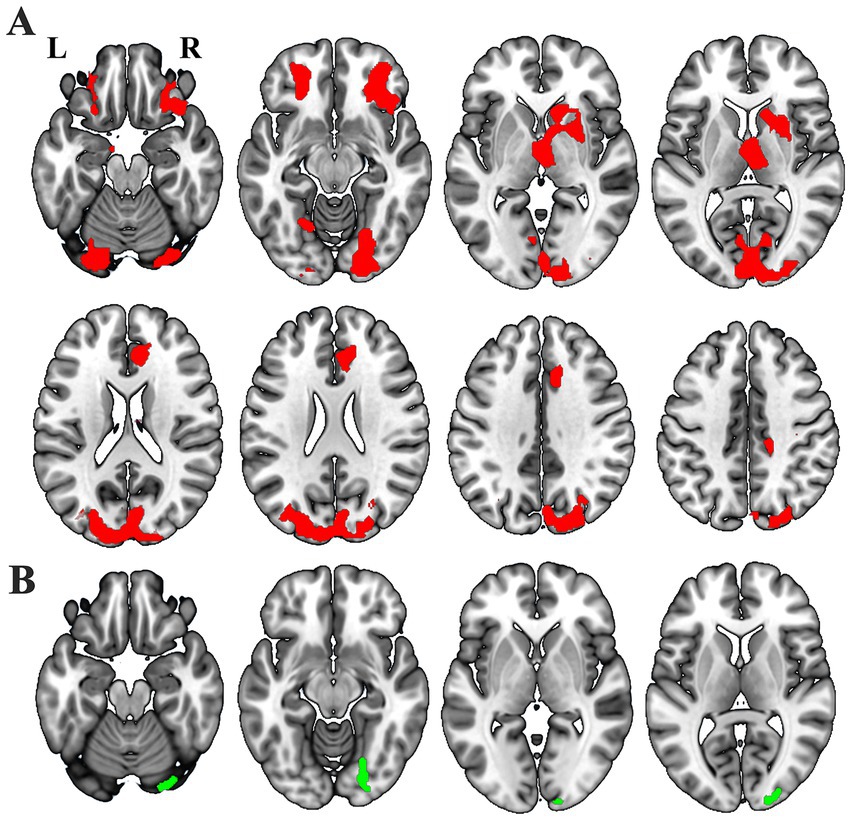

Voxel-wise GLM analysis revealed significant changed SCN between either one of the thalamic subfields and widespread of brain regions (Figure 3A), including the bilateral orbitofrontal cortex (OFC), bilateral dorsal and ventral visual cortex, ipsilesional thalamus, ipsilesional caudate, ipsilesional striatum, bilateral the anterior cingulate cortex (ACC), and so on. In contrast, increased SCN was only shown between the ipsilesional ventral visual cortex and the whole thalamus (Figure 3B) (p < 0.05, cluster-wise FWE correction).

Figure 3. Different masks showthe notable GMV covariance results: thalamic subfields (A, red) and entire thalamus (B, green).

We observed notably increased SCN for 16/25 ipsilesional thalamic subfields, including AV, LD, LP, VLa, VLp, VPL, VM, CeM, CL, MDm, LGN, PuM, PuI, CM, Pf and Pt (Figure 4A). Besides, we found 3/25 contralesional thalamic subfields showing increased SCN with the ipsilesional OFC, thalamus and striatum (Figure 5A).

The thalamus comprises functionally differentiated subfields, with distinct nuclei mediating specialized neural processes (Corona et al., 2020; Iglesias et al., 2018). The fundamental limitation of whole-thalamus analyses stems from the forced homogenization of inherently heterogeneous structures (Yuan et al., 2015), which obscures subfield-level functional antagonism or complementary patterns through artificial neutralization. While this simplification reduces analytical complexity, it critically compromises the understanding of fine-grained thalamic functional architecture and the pathophysiological mechanisms underlying thalamic-related disorder (Antonucci et al., 2021; Lin et al., 2018; McKenna et al., 2023; Yang et al., 2023). The high-resolution thalamic segmentation framework proposed by Iglesias et al. (2018) enables subfield-level structural covariance network (SCN) analysis, substantially enhancing our capacity to detect post-stroke thalamocortical network pathology. In our study, the whole-thalamus analysis identified only ipsilesional ventral visual cortex-thalamus SCN enhancement (Figure. 3B). In contrast, subfield-specific analysis revealed significant GMV covariance alterations in 16/25 ipsilesional and 3/25 contralesional thalamic subfields (Figures 4A, 5A), demonstrating the superior sensitivity of subfield-level approaches—consistent with prior studies showing that subfield decomposition uncovers otherwise hidden network changes (d'Ambrosio et al., 2017; Tung et al., 2022). Analogous methodology in schizophrenia research highlights the value of subfieldal decomposition—amygdala subfield analysis reveals more extensive GMV covariance abnormalities and distinct subfieldal engagement patterns, advancing understanding of limbic pathophysiology (Chang et al., 2024). These convergent findings underscore the critical advantage of subfield-level paradigms in elucidating network-level neuropathology.